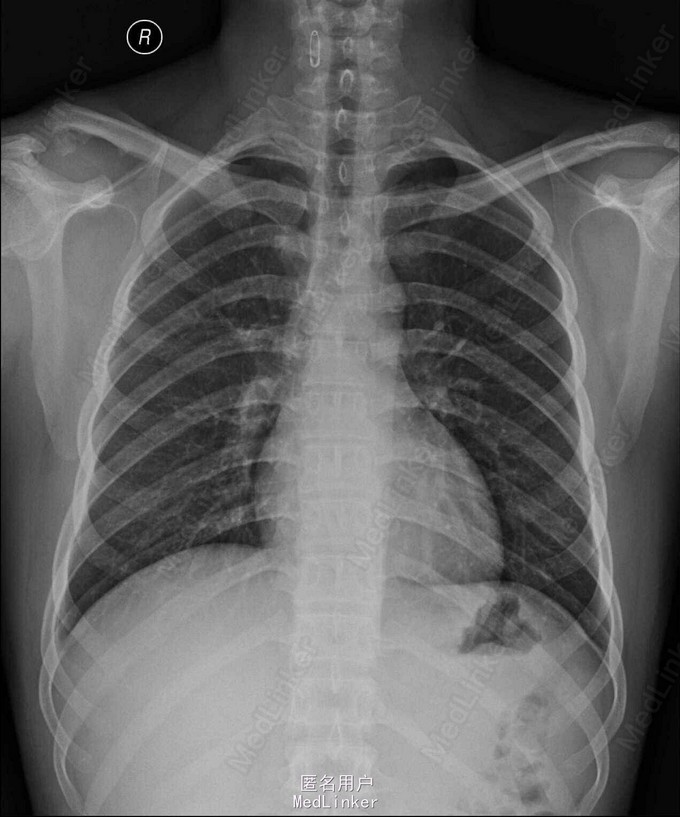

主诉: 外伤致右肩关脱位伴活动障碍10月余 病史: 患者缘于10月前患者训练时受伤致右肩关节疼痛,伴活动障碍,以上举、内收、背伸时明显,当地予以制动、止痛等对症支持治疗,其后反复发作,未予以重视,1周前,上述症状加重,行右肩关节MRI提示:右锁骨肩峰端骨质结构稍乱伴小片状高信号,考虑损伤后改变可能,建议住院进一步检查及治疗,门诊予以“右肩锁关节脱位”收入我科

查体:步入病房,右上肢绷带悬吊于胸前,拆开绷带见:右肩关节活动障碍,未见瘀斑,压痛、畸形,未闻及骨摩擦音,未扪及骨擦感,右上肢活动受限,以上举、外展、背伸明显,右尺桡动脉搏动尚可,右上肢感觉未见明显异常,余肢体查体未见明显异常,辅助检查见影像

诊断:右锁骨远端陈旧性骨折伴肩锁关节脱位肩锁关节 治疗: 右锁骨远端骨折切开探查骨块摘除,肩锁关节脱位复位克氏针固定,喙锁韧带重建术